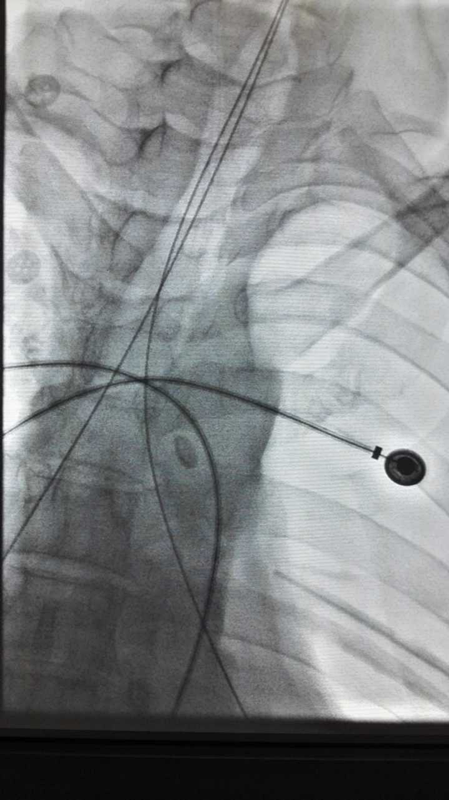

我院胸外科以李少民教授、张晋主治医师等组成的治疗团队,利用气管带膜支架置入术对该例患者进行治疗,取得满意效果。术中利用支气管镜直视下向左、右主支气管分别置入金属导丝,利用X线透视确定位置无误。

沿着导丝将“Y型”气管带膜支架的两个臂逐渐置入两侧主支气管。确认位置无误后退出导丝,再次确定支架位置。左侧支架远端为盲端,封堵瘘口,右侧支架远端通畅,维持右侧支气管系统通气功能。